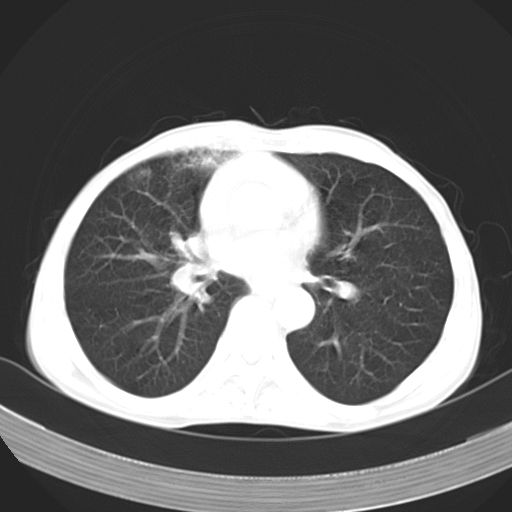

以下是引用苯小孩在2007-5-24 12:47:00的发言:[br]右侧肺门处不均匀密度软组织块影,远端肺组织见斑片模糊影,纵隔内淋巴结明显肿大,边界不清.<纵隔窗第12层面支气管内似见软组织结节>[br]考虑:1、右侧中央性肺癌并阻塞性肺炎并纵隔淋巴结转移可能性大.建议强化或纤支镜进一步检查.[br]2、隆突下淋巴结肿大/食道病变?请做鉴别检查.

以下是引用jw-830在2007-5-24 15:24:00的发言:[br][br] [br] 考虑右肺中央型肺癌并阻塞性炎症,右肺门及纵隔淋巴结转移。 [br] [br][br]